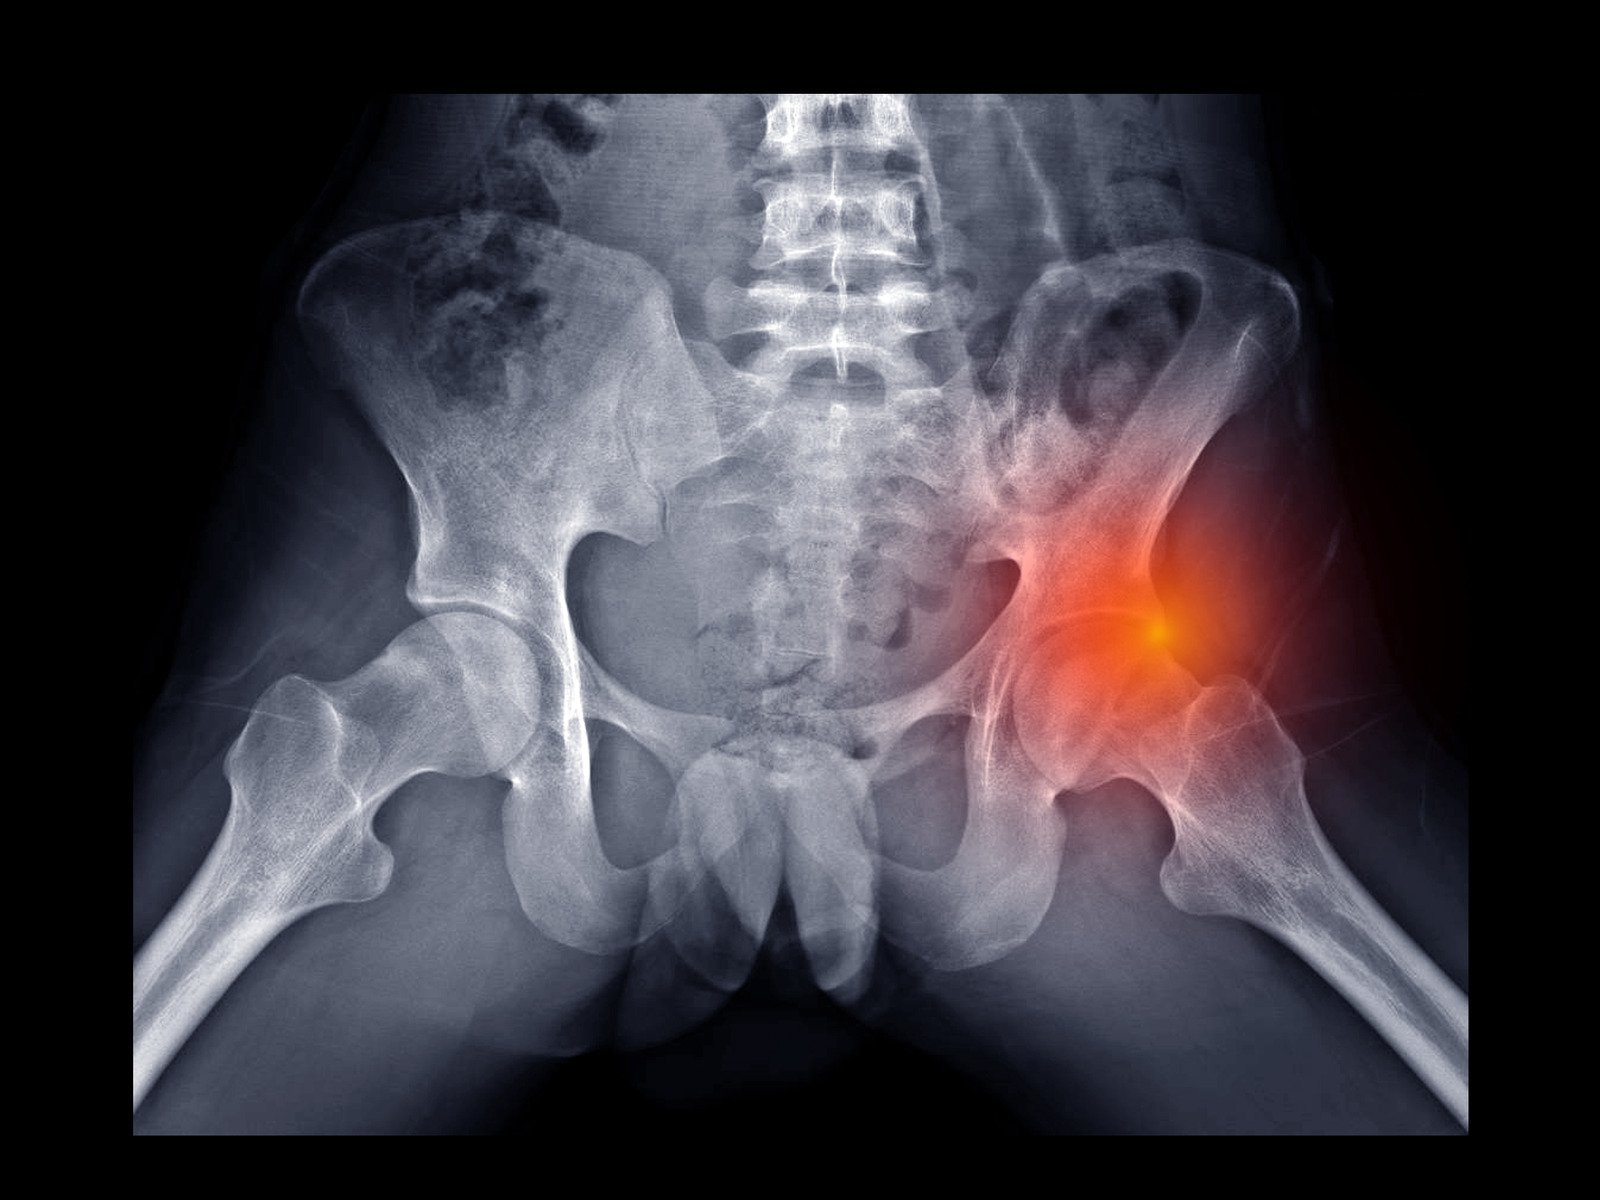

관절순 파열(Labral Tear)은 고관절이나 어깨 관절의 연골 조직인 관절순이 찢어지는 상태를 의미합니다.

관절순은 고관절과 어깨 관절에 있는 섬유연골 조직으로, 관절 주위에 위치하여 관절의 움직임을 안정화하고 충격을 흡수하는 역할을 합니다.

관절순은 관절을 감싸는 얇고 강력한 구조물로, 관절의 원활한 움직임을 돕습니다.

X-레이: 다른 관절 문제를 배제하기 위해 사용될 수 있습니다.